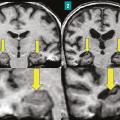

Décrit initialement en 1881 chez des alcooliques, en association avec une polyneuropathie, l’origine du syndrome de Korsakoff est éthylo-carentielle. Depuis lors, d’autres causes carentielles ont été identifiées, parmi lesquelles l’hyperémèse gravidique (vomissements incoercibles du premier trimestre de la grossesse) ou les complications de la chirurgie bariatrique. Leur point commun est la carence en vitamine B1, à l’origine d’une nécrose hémorragique des corps mamillaires (fig. 4) et/ou des lésions des noyaux antérieurs et dorso-médians du thalamus,4 qui interrompent de façon bilatérale le circuit de Papez (voir l’article « Anatomie de la mémoire » page 1072 ).